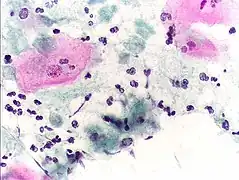

Classically, with a cervical smear, infected women may have a transparent "halo" around their superficial cell nucleus but more typically the organism itself is seen with a slight cyanophilic tinge, faint eccentric nuclei, and fine acidophilic granules.[30] It is unreliably detected by studying a genital discharge or with a cervical smear because of their low sensitivity. T. vaginalis is also routinely diagnosed via a wet mount, in which "corkscrew" motility is observed. Currently, the most common method of diagnosis is via overnight culture,[31][32] with a sensitivity range of 75–95%.[33] Newer methods, such as rapid antigen testing and transcription-mediated amplification, have even greater sensitivity, but are not in widespread use.[33] The presence of T. vaginalis can also be diagnosed by PCR, using primers specific for GENBANK/L23861.[34]

- Pap smear, showing infection by Trichomonas vaginalis. Papanicolaou stain